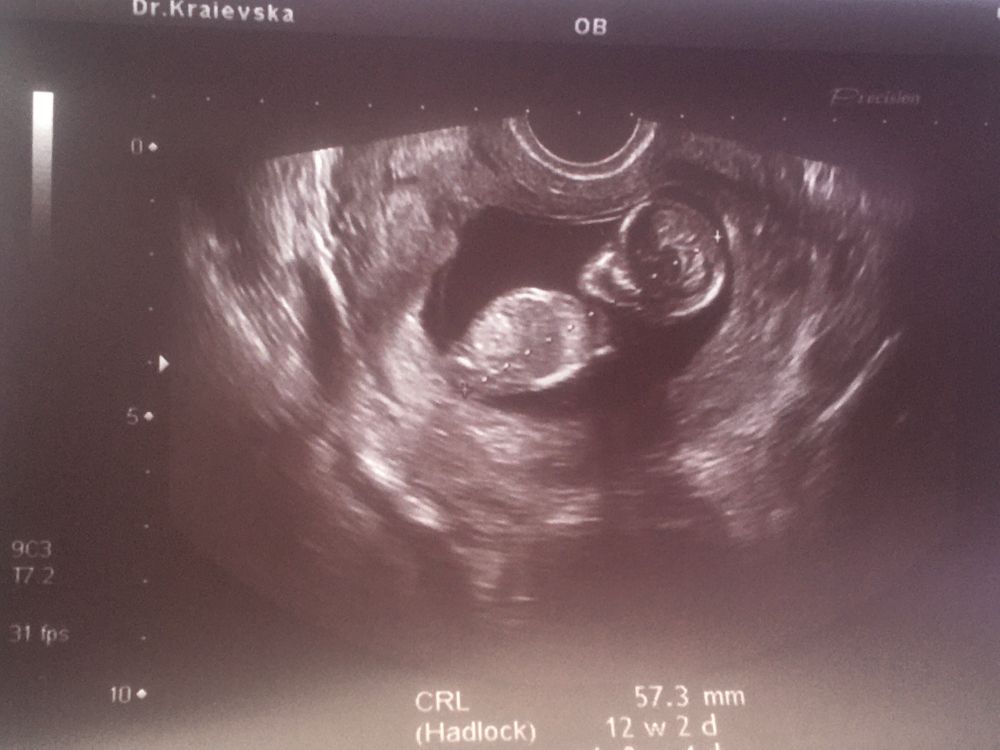

Чашка утреннего кофе,

если Вам не трудно можете у меня определить)) я решила посмотреть узи девочек и мальчиков) и все равно ничего не поняла)

Julia, на этом снимке ничего не видно, очень маленькое и нечёткое изображение. А срок тут какой?

Julia, маловато для определения по половому бугорку, всё ещё слишком маленькое) недель в 12 нужно смотреть хотя бы, да и то на таком сроке пока вероятность ошибки велика. Если очень любопытно, сдайте кровь на определение пола)